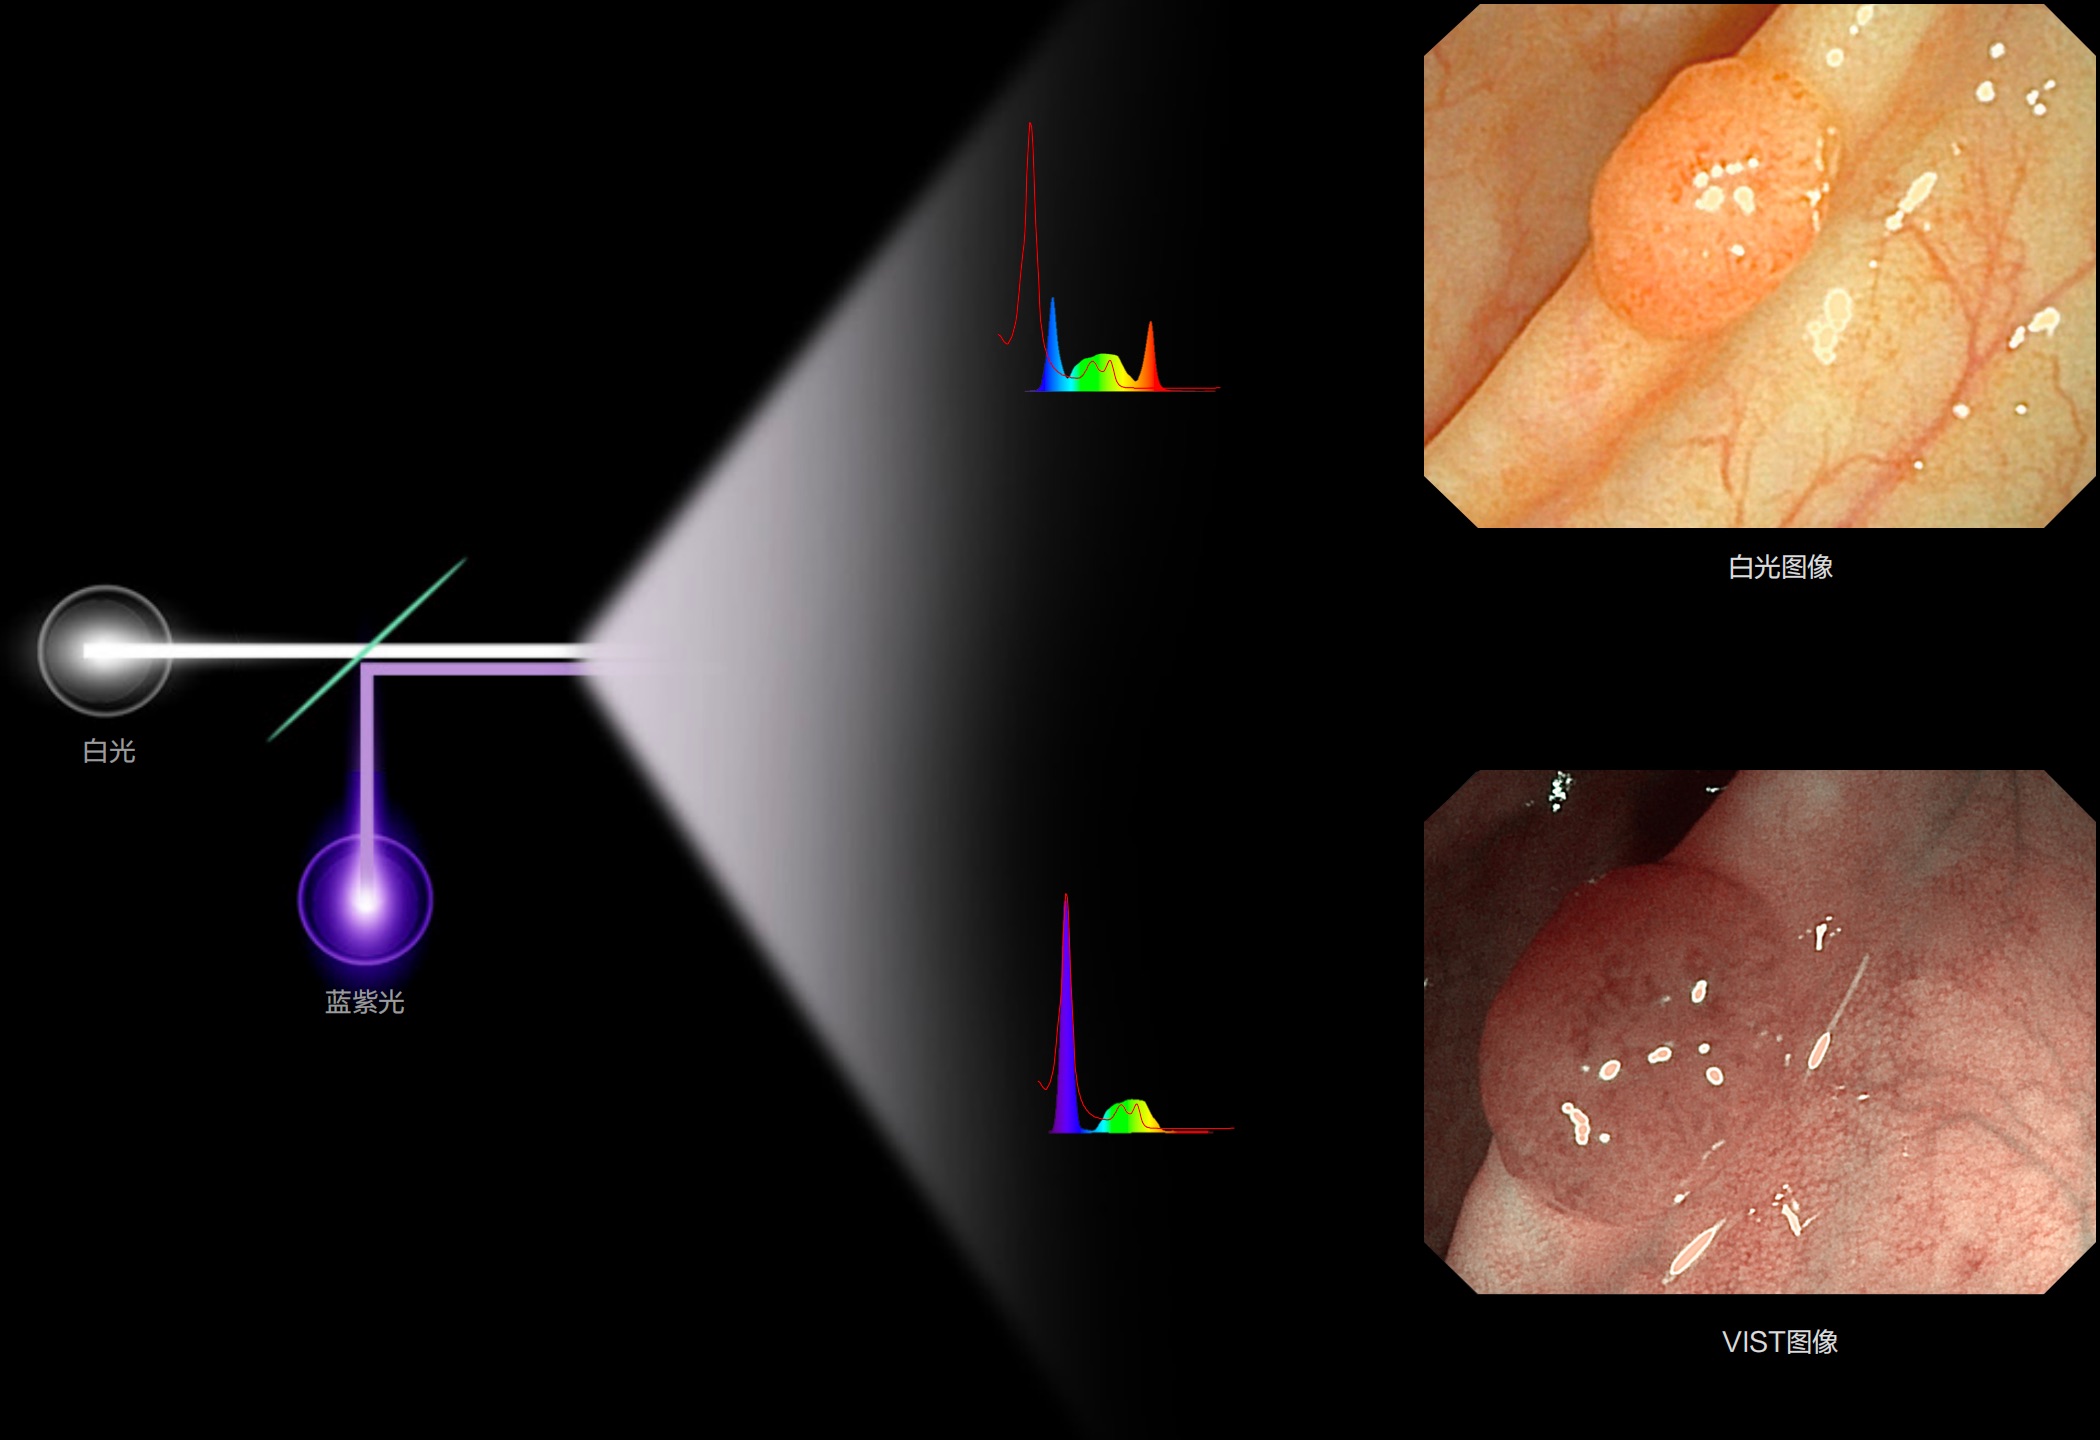

(Spectral Focused lmaging, SFI)

能够凸显黏膜浅层和中层血管轮廓,适用于中、远景观察下的病灶识别和早癌筛查。

(Versatile Intelligent Staining Technology)

能够凸显黏膜浅层血管轮廓和黏膜表面微结构,适用于中、近景观察下的早癌精确诊断。